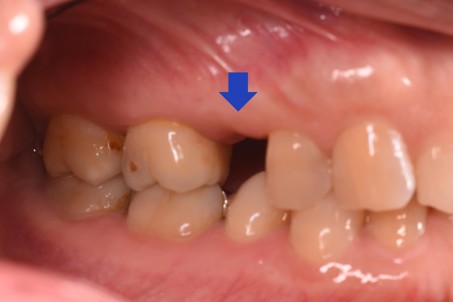

治療前

長期間、歯が無いままになっていたため隣の歯が動いてきてしまっており新しく歯を入れる隙間が減ってきている状態でした |